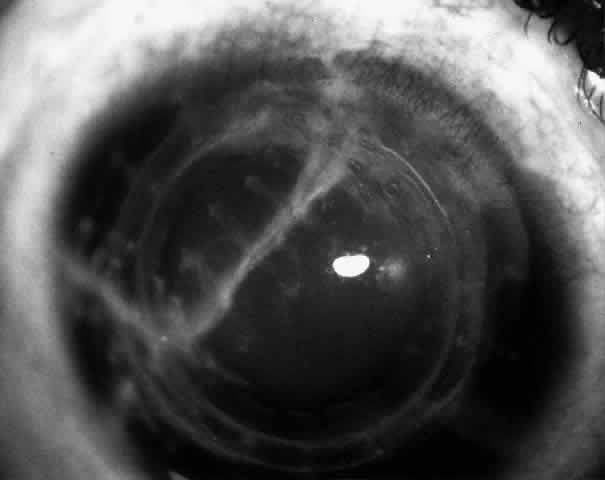

Children who have traumatic cataracts with corneal lacerations are well served by this procedure because the injury often destroys the capsular support that can be used to stabilize an intraocular lens.16–18 The epikeratophakia graft provides structural support for the weakened cornea and minimizes the induced irregular and regular astigmatism, in addition to correcting the optical error (Figs. 3 AND 4).

Fig. 3. Lacerated cornea with a hyphema. (Morgan KS, Ellis GS, Marvelli TL, Arffa RC: Epikeratophakia in children with traumatic cataracts. J Pediatr Ophthalmol Strabismus 23: 108–113, 1986)